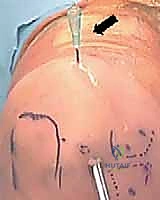

- التموضع الجراحي: يوضع المريض في وضعية الاستلقاء الجانبي أو الانبطاح، مع تعليق الذراع وتأمينها بعناية لفتح مساحة المفصل.

- إنشاء المنافذ (Portals): في حالة التنظير، يتم عمل 2 إلى 4 ثقوب دقيقة جداً في نقاط آمنة تشريحياً لتجنب الأعصاب والأوعية الدموية.

- الإغلاق: يتم خياطة الشقوق الصغيرة بغرز تجميلية، وتوضع ضمادات معقمة، ثم توضع الذراع في جبيرة أو دعامة لحمايتها.